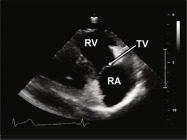

| 2.6. Mặt cắt trục dài cạnh ức qua buồng nhận thất phải |

||||||||

|

|

Cửa sổ siêu âm cạnh ức

Mặt cắt trục dài cạnh ức Ngả đầu dò xuống dưới hướng về phía đùi phải của bệnh nhân |

Nhĩ phải (RA) Van ba lá (TV) Thất phải (RV) |

|||||